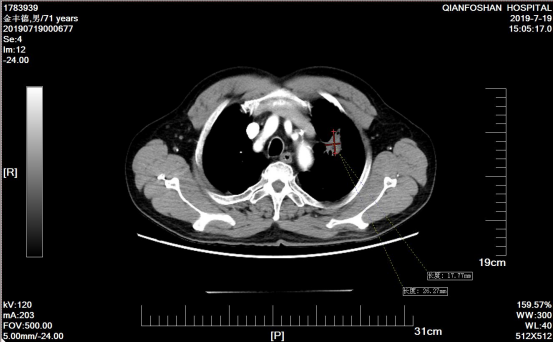

患者氩氦刀治疗后11个月复查肿瘤CT影像

经过再次病理检查,李老伯患的确是肺鳞状上皮细胞癌,所以氩氦刀治疗后仍需定期复查,并进行正规化疗。根据刘元水的意见,李老伯每3-4个月回来复查,调整治疗方案,期间可以按照治疗方案在当地医院进行治疗。就像一个约定,此后4年,李老伯风雨无阻,定期从商河赶到山一大一附院复诊。肿瘤微创科医生魏有国介绍说,“患者左肺肿瘤逐渐缩小,病情稳定、治疗过程也很顺利。”四来年,魏有国作为李老伯的主管医师,一直负责他的治疗。“太感激刘主任和魏大夫了,是他们帮我战胜癌症!这里不仅专家好、技术好,能治病,护士也好,服务细致周到,给了我很多帮助和关心。”